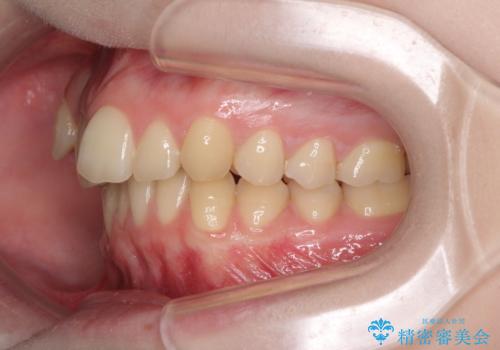

八重歯を短期間で改善 ワイヤー装置による抜歯矯正

- 著しい八重歯を気にして来院された患者様です。

片側の八重歯であり上顎の正中がずれていたため、上顎左右第一小臼歯2本を抜歯して排列することとしました。

下顎の骨格的なズレが大きかったため、上下歯列のバランスが取れるか心配でしたが、上下ともに左右対称に近い歯列で治療を終えることができました。